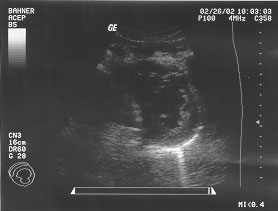

Cardiac - long parasternal (unlabeled)